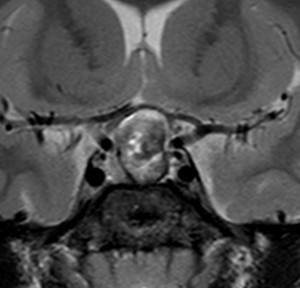

成人の第3脳室内部に局在する頭蓋咽頭腫です。経脳梁法で両側のモンロー孔から全摘出しました。下垂体組織は残っています。これは乳頭状頭蓋咽頭腫と呼ばれるもので,成人にしか発生しません,のう胞がなく石灰化もないのが大きな特徴です。境界が明瞭で柔らかく摘出が簡単なタイプとして知られています。この患者さんも術後に下垂体機能不全も視床下部障害も生じませんでした。